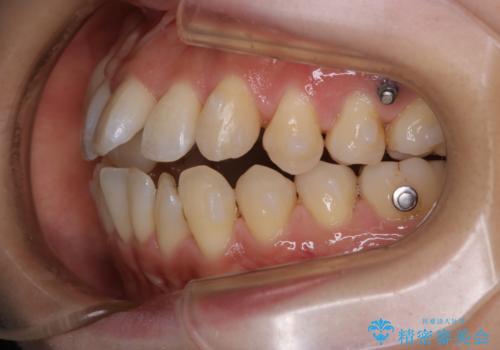

- インビザラインで矯正中に着色や歯石がついてしまったためクリーニングをしたいとのことで来院されました。

PMTC60分コースを行いました。

コーヒーによる頑固な着色や磨き残しによる歯石が多く付着していました。マウスピースをつけたままコーヒーを飲むこともあるそう。その場合は、なるべくはやくに歯磨きをしてマウスピースもしっかりと洗いましょう。

※マウスピースの装着中はお水を飲んでください。